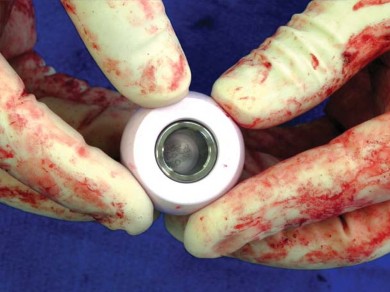

الزرعة نظام Taperloc Microplasty

يفضل الأستاذ الدكتور محمد هطيف استخدام نظام Taperloc® Microplasty من شركة Biomet (وارسو، إنديانا)، وهو أحد الخيارات المتاحة للزرعات الخالية من الأسمنت. يعتمد هذا النظام على تصميم إسفيني مخروطي وسطي-جانبي بدون ياقة، مصمم للتثبيت الذاتي والاستقرار الدوراني.

- المادة والتصميم: مصنوع من التيتانيوم (Ti-6AL-4V) ويتميز بطلاء مسامي رش بلازما محيطي قريب. تستخدم Biomet تقنية خاصة لتطبيق الطلاء المسامي بحيث لا يتم تسخين الزرعة بشكل كبير، مما يحافظ على مستويات عالية من مقاومة الإجهاد.

- الأحجام والتنوع: تتوفر السيقان في أحد عشر حجمًا، تتراوح أطوالها من 95 ملم إلى 130 ملم، وتزداد تدريجيًا جانبيًا بينما يظل الانحناء الأنسي ثابتًا. زاوية عنق-جذع 138 درجة، وهناك خياران للإزاحة: قياسي وجانبي.

- تقنية التحضير: باستثناء موسع الفتحة، لا يتطلب النظام أي كشط؛ فهو نظام يعتمد على التوسيع فقط، مما يسهل الإجراء ويقلل من إزالة العظام.